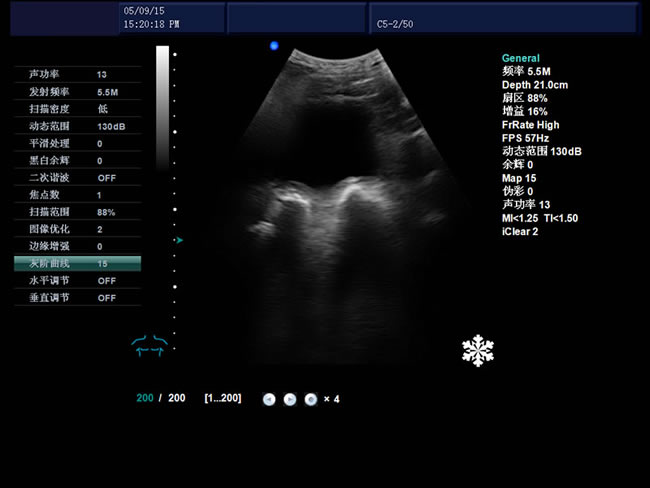

S9 彩色多普勒獸用超聲診斷儀

• S9彩色多普勒獸用超聲診斷儀是徐州市大為電子設備有限公司推出的一款全新的彩色超聲診斷儀器。

電影回放存儲